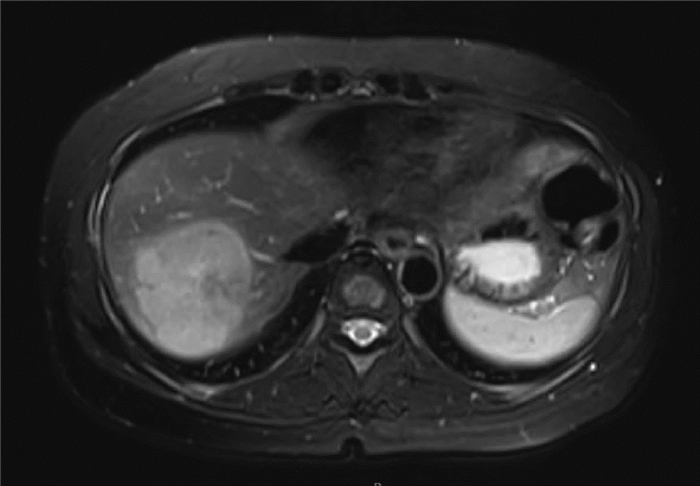

肝滤泡树突细胞肉瘤1例报告

李晨光, 贾继尧, 孙栾彪, 高硕徽

2022, 38(1): 174-176. DOI: 10.3969/j.issn.1001-5256.2022.01.029

摘要(1615) HTML (456) PDF (2854KB)(68)

摘要: